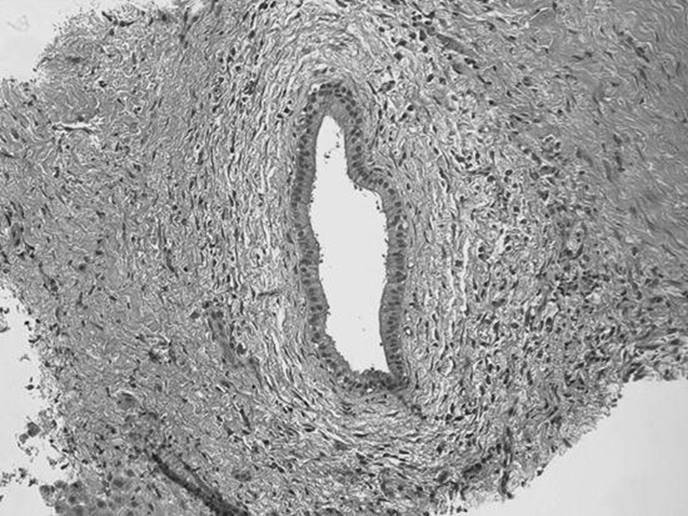

What liver condition is being demonstrated in the figure below? In this condition, what type of collagen is deposited to an excessive degree and what cell is its source?

Figure 51-1

Cirrhosis. Collagen of types I and III produced by the Ito cell. The Ito cell functions as a storage vehicle, metabolizes vitamin A, and aids in the production of collagen.